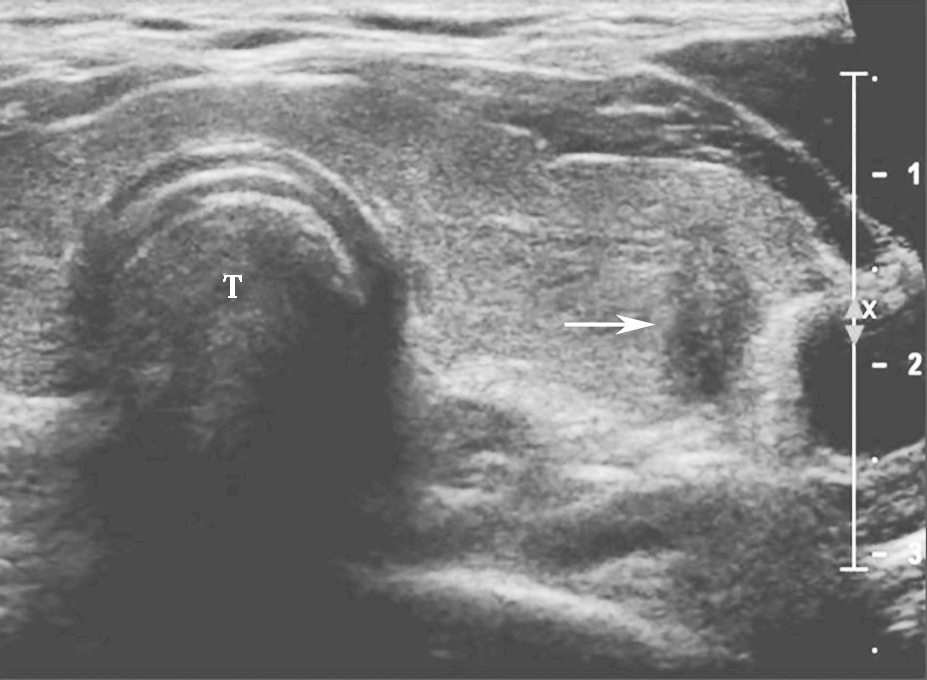

甲状腺滤泡癌和滤泡腺瘤在超声上鉴别有一定困难,即使是FNA细胞学也很难鉴别。但有报道认为:与甲状腺乳头状癌不同,甲状腺滤泡癌常为等回声或高回声,微小钙化很少见,病变多伴有厚薄不一的低回声晕或者局部低回声晕。彩色多普勒血流信号丰富也是该类病变的特点之一(图11、图12)。

图11右侧颈部纵切面:甲状腺右叶中部中等回声(箭头所示):内部回声不均伴厚薄不一低回声晕

图12右侧颈部纵切面(与图3-3-11同患者、同切面):中等回声彩色多普勒血流信号丰富而杂乱